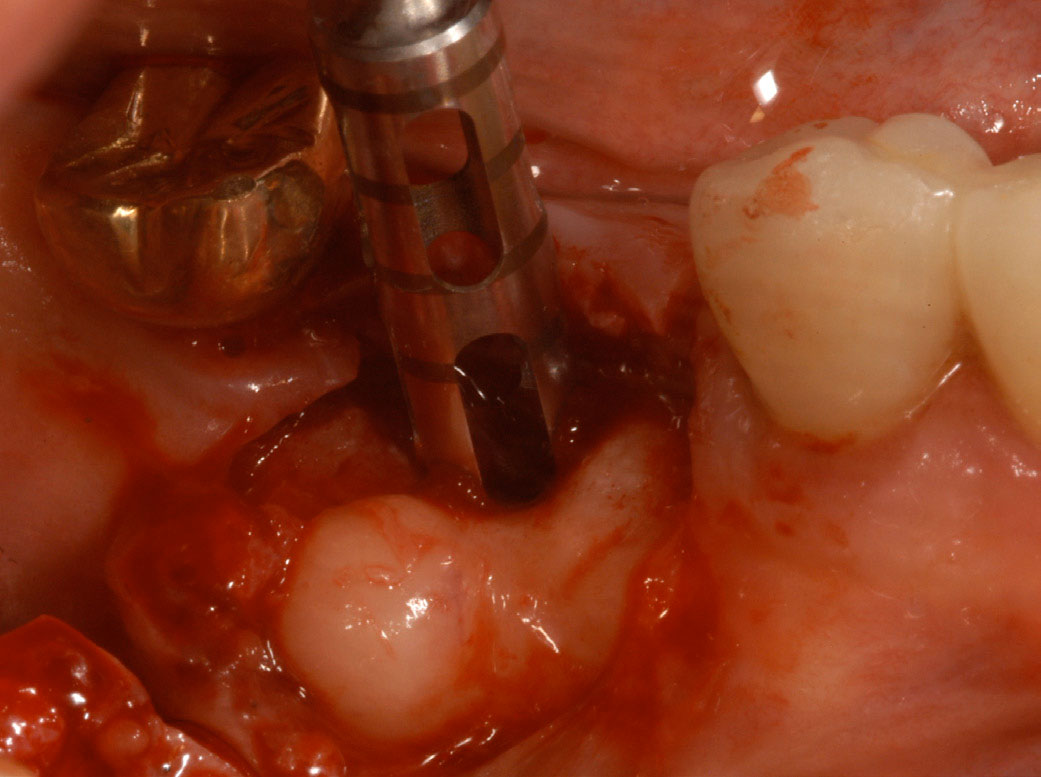

Figure 11 – Internal connection implant system – implant placed post-extraction

Figure 11

Figure 12 – Prefabricated zirconia abutment fitting the internal connection in Figure 11

Figure 12

Figure 13 – Zirconia abutment torque onto implant

Figure 13

The implant platform can also have different shapes. It can have an internal or external platform with the abutment. The original Brånemark system had an external connection. The internal connection platform is the most preferred method used now in dental practices (Figure 11 through Figure 13).